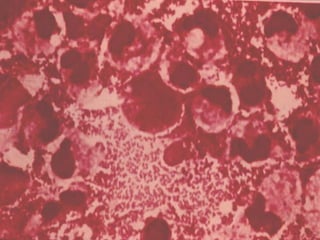

MENINGITIS BACTERIANA Anatomía Patológica: Hallazgos microscópicos: Microhemorragias en Aracnoides y Piamadre. Proliferación de microglia. Destrucción de células ependimarias. Infiltración de P.M.N. EDEMA.

MENINGITIS BACTERIANA AnatomíaPatológica: Hallazgos microscópicos: Microhemorragias en Aracnoides y Piamadre. Proliferación de microglia. Destrucción de células ependimarias. Infiltración de P.M.N. EDEMA.